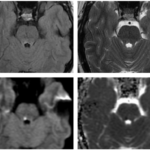

El presente caso ilustra un infarto isquémico del mesencéfalo medial, con una distribución paramediana bilateral y predominio a nivel del tegmento, acompañado de extensión caudal limitada hacia la unión pontomesencefálica. Este patrón topográfico, identificado mediante la combinación de secuencias de difusión y mapas ADC, es característico de la afectación de las ramas perforantes paramedianas del segmento distal de la arteria basilar y/o del segmento proximal de la arteria cerebral posterior, responsables de la irrigación del mesencéfalo medial, y ha sido descrito en infartos mesencefálicos mediales bilaterales dependientes de estas ramas perforantes.(5, 16)

En términos topográficos, la bilateralidad y simetría de la lesión constituyen un elemento clave para su correcta interpretación. A diferencia de los síndromes mesencefálicos alternos clásicos, como los síndromes de Weber o Benedikt, en los que el compromiso es típicamente unilateral y se extiende hacia los pedúnculos cerebrales, en este caso la lesión se encuentra confinada al tegmento medial, sin afectación significativa de las estructuras laterales, patrón previamente reportado en series imagenológicas de infartos mesencefálicos mediales.(5, 16) Este hallazgo permite descartar un patrón peduncular y refuerza el diagnóstico de un infarto mesencefálico medial.

La extensión rostro-caudal observada, con compromiso adicional del puente rostral, no debe interpretarse como la coexistencia de lesiones independientes, sino como la expresión de un territorio vascular continuo, fenómeno descrito en infartos dependientes de perforantes paramedianas largas.(17, 18) En este contexto, el análisis del eje rostro-caudal resulta tan relevante como la evaluación dorsoventral, en especial en lesiones localizadas en zonas de transición anatómica.

En este caso, la lesión se localiza predominantemente a nivel del mesencéfalo medial, con una distribución paramediana bilateral y extensión caudal limitada hacia la unión pontomesencefálica. Este patrón topográfico permite integrar los hallazgos imagenológicos dentro de un infarto mesencefálico medial y diferenciarlos de otros síndromes mesencefálicos clásicos con compromiso lateral o peduncular.(5)